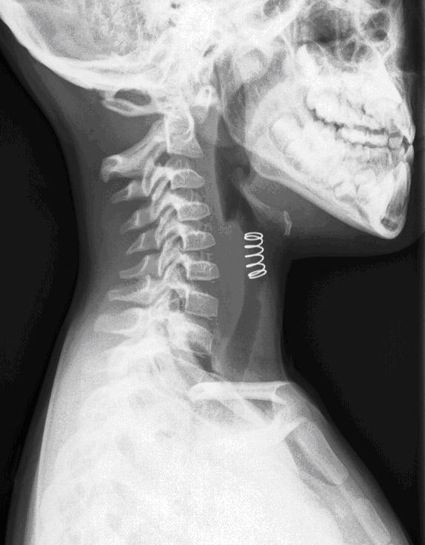

Si no hay un compromiso de las vías respiratorias, una radiografía de tórax puede revelar un cuerpo extraño radiopaco.

La detección de cuerpos extraños radiolúcidos puede ser ayudada por TC o películas de inspiración-exhalación que demuestran la captura de aire distal al segmento obstruido.